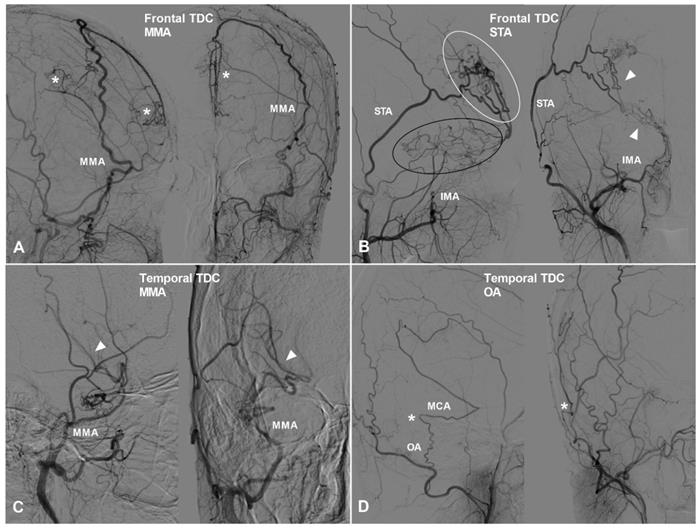

TDCs to the other surfaces of the frontal lobe and the other lobes

Apart from TDCs at the anterior cranial fossa, the frontal lobe can also receive collateral circulation at its lateral, superior, and medial surfaces. The MMA, superficial temporal artery (STA), and FA could pierce the dura mater and anastomose with the cortical arteries of the frontal lobe. Furthermore, we have also studied TDCs to the temporal, parietal, and occipital lobes. TDCs from the MMA, STA, and FA are illustrated in Figure 3 and 4.

Figure 3

The frontal and temporal TDCs. A, Angiogram of the ECA in lateral (left) and AP (right) views shows the MMA provides TDC by anastomosing with the midline arteries (asterisk). B, Angiogram of the ECA in lateral (left) and AP (right) views shows the STA (white oval) and IMA (black oval) provide TDCs to the brain. Besides, the STA and IMA also form anastomosis (arrow head). C, Angiogram of the ECA in lateral (left) and AP (right) views shows TDC from the MMA anastomoses with the MCA (arrow head). D, Angiogram of the ECA in lateral (left) and AP (right) views shows TDC from the OA anastomoses with the MCA (asterisk). Abbreviations: ECA, external carotid artery; IMA, internal maxillary artery; MMA, middle meningeal artery; OA, occipital artery; TDC, transdural collateral.

Figure 4

The parietal and occipital TDCs. A, Angiogram of the ECA in lateral view shows a small parietal TDC originates from the MMA (oval). B, Angiogram of the ECA in lateral view shows the MMA provides extensive TDCs to the parietal cortex. C, Angiogram of the ECA in lateral view shows the MMA originating from the OphA provides TDC (oval) to the parietal cortex. D, Angiogram of the ECA in anteroposterior view shows the OA provide TDC (circle) to the parietal cortex. E, Angiogram of the ECA in lateral view shows TDC (oval) from the MMA anastomoses with the MCA at the occipital cortex. F, Angiogram of the ECA in lateral view shows TDC (oval) from the OA anastomoses with the occipital cortical arteries. G, Angiogram of the VA in lateral view shows TDC (oval) from the PMA anastomoses with the occipital cortical arteries. H, Angiogram of the ECA in lateral view shows TDCs (oval) from the PMA and MMA anastomose with the occipital cortical arteries. Abbreviations: ECA, external carotid artery; MCA, middle cerebral artery; MMA, middle meningeal artery; OA, occipital artery; OphA, ophthalmic artery; PMA, posterior meningeal artery; TDC, transdural collateral; VA, vertebral artery.